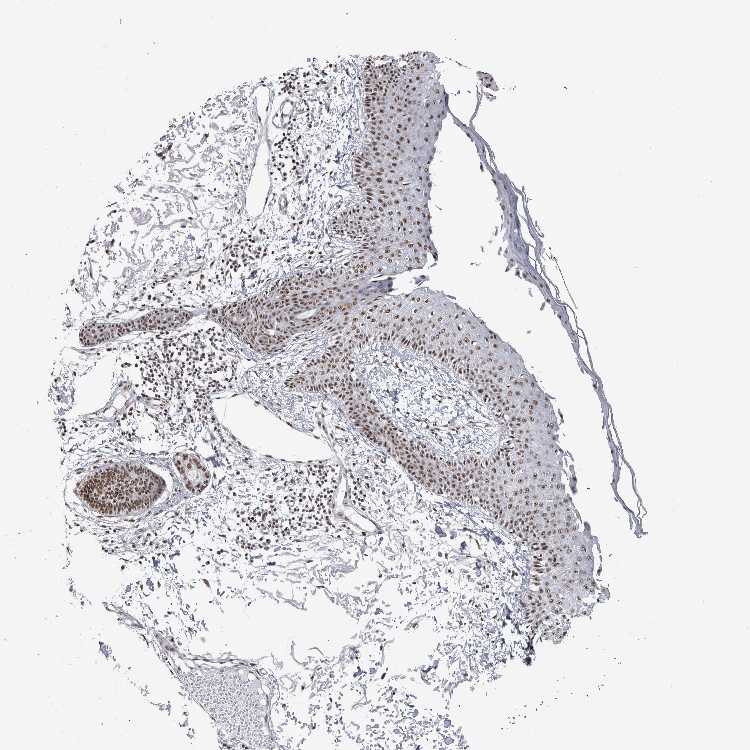

SKIN 2 - Antibody stainingi

Antibody staining in the annotated cell types in the current human tissue is reported as not detected, low, medium, or high, based on conventional immunohistochemistry profiling in selected tissues. This score is based on the combination of the staining intensity and fraction of stained cells.

Each image is clickable and will lead to virtual microscopy that enables deeper exploration of all samples and also displays staining intensity scores, fraction scores and subcellular localization as well as patient and tissue information for each sample.

Antibody HPA024331

Epidermal cells High